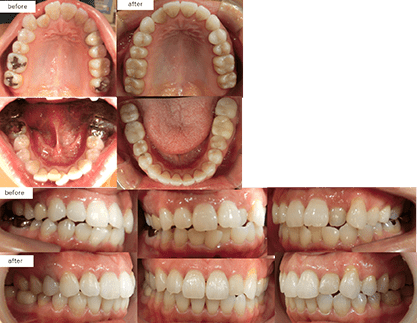

治療方法 床矯正で上下横に拡大しインビザラインへ移行、親知らず抜歯あり 治療の説明 主訴:叢生、

上下の前歯叢生が気になる年齢 26歳 ![]()

治療費用 877,800円(税込)

(インビザライン767,800円 床矯正2装置110,000円)治療期間 2年4カ月 通院回数 17回 治療の副作用(リスク) 元々隙間が開いていたところはしっかり保定装置を入れておかないと後戻りする可能性があります。咬合痛、歯根吸収、歯根露出が生じる可能性があります。 歯科医師からのコメント 元々上下の前歯が噛み合っておりませんでしたが、上の前歯を後ろに下げることで前歯のかみ合わせも良くなっています。